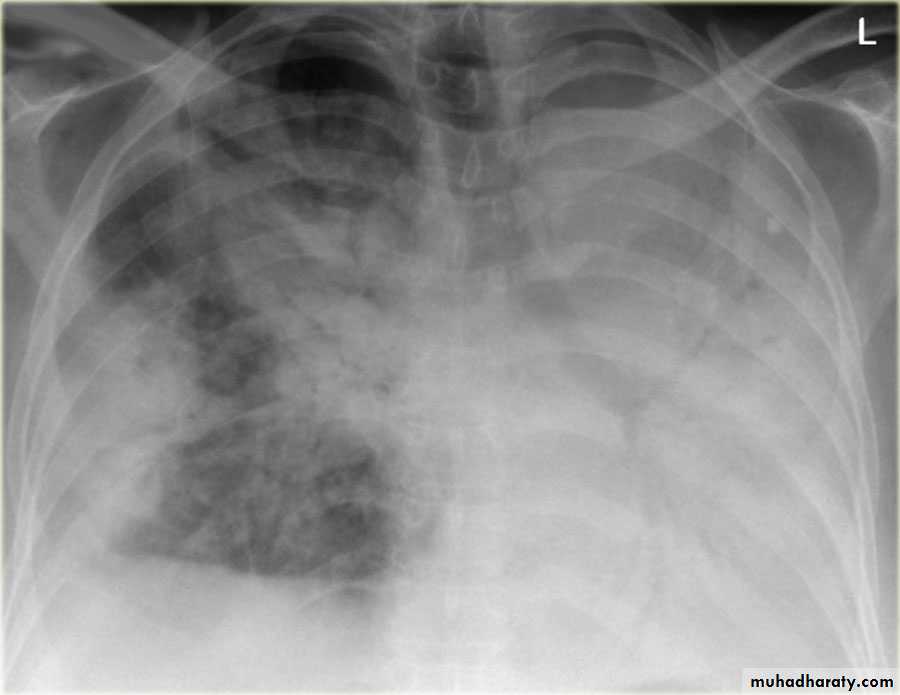

Fall from the 2nd floor